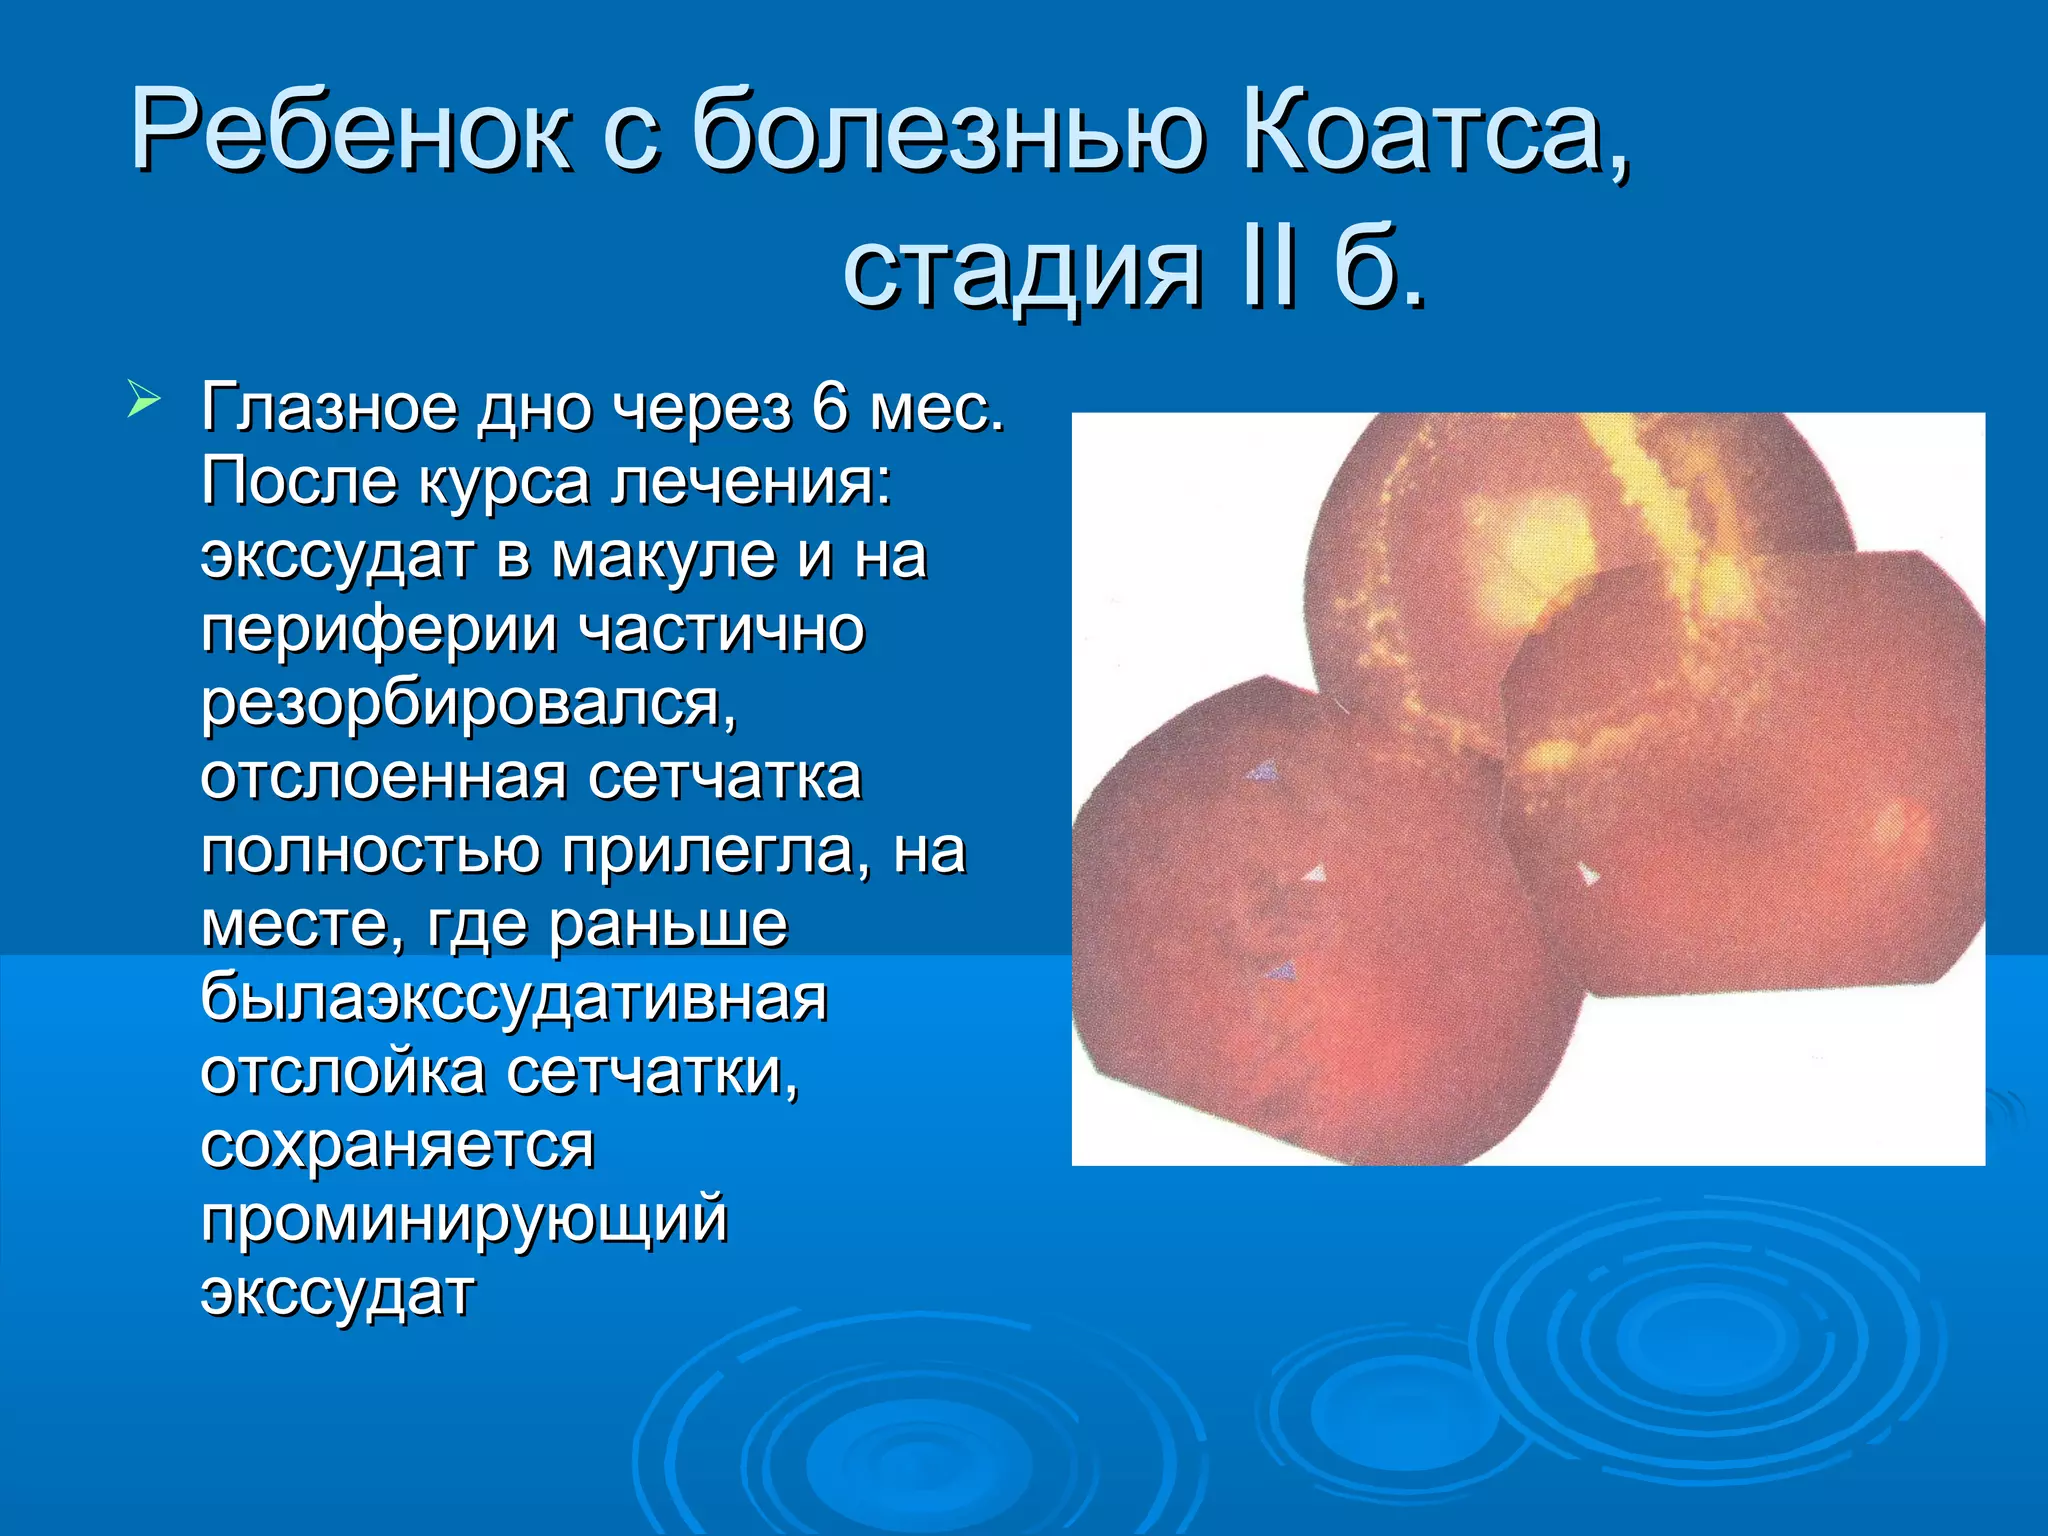

Болезнь Коатса - это идеопатическое заболевание, характеризующееся полиморфными изменениями сосудов сетчатки с массивной экссудацией, чаще всего у детей и подростков, с преобладанием среди мальчиков. Эпидемиология показывает, что заболевание проявляется, как правило, в возрасте 8-16 лет, но возможно его обнаружение и у взрослых. Основные проявления включают ретинальные аномалии, субретинальную экссудацию и постепенно прогрессирующую потерю зрения.